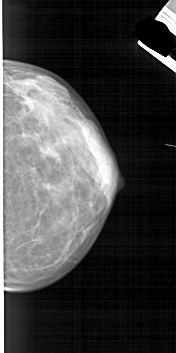

ics_version 1.0 filename A-1841-1 DATE_OF_STUDY 9 8 1996 PATIENT_AGE 45 FILM FILM_TYPE REGULAR DENSITY 4 DATE_DIGITIZED 18 5 1999 DIGITIZER HOWTEK 43.5 SEQUENCE LEFT_CC LINES 4636 PIXELS_PER_LINE 2326 BITS_PER_PIXEL 12 RESOLUTION 43.5 OVERLAY LEFT_MLO LINES 5041 PIXELS_PER_LINE 2626 BITS_PER_PIXEL 12 RESOLUTION 43.5 OVERLAY RIGHT_CC LINES 4936 PIXELS_PER_LINE 2461 BITS_PER_PIXEL 12 RESOLUTION 43.5 NON_OVERLAY RIGHT_MLO LINES 5491 PIXELS_PER_LINE 2551 BITS_PER_PIXEL 12 RESOLUTION 43.5 NON_OVERLAY |